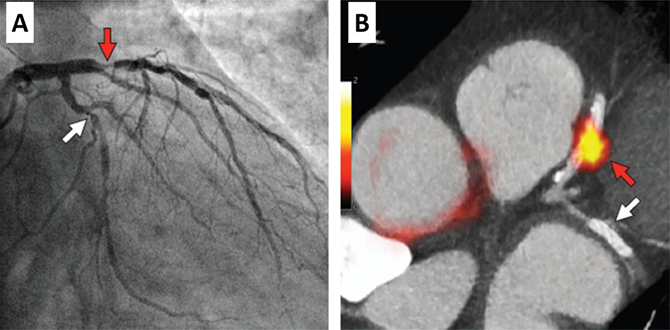

근적외선 분광법(NIRS)은 미국 FDA 승인을 받은 혈관 내 영상 기법으로, 근적외선에 의해 지방 성분의 화학적 특성을 식별하는 방식을 사용하여 동맥경화반의 지방을 정량화하며, 최근 취약성 경화반을 평가하는데 그 유용성을 인정받고 있다 (그림 3). 최근 Oemrawsingh 등은 관상동맥 영역에서 NIRS 에 의해 검출된 지방의 양과 관련한 예후를 평가한 전향적 연구 결과를 발표하였다. 이 연구에 의하면 NIRS 에 의해 감지된 지방이 풍부한 경화반은 그렇지 않은 경우 보다 심근경색과 같은 심혈관 사건(cardiovascular event)의 발생률이 약 4배가량 높다고 보고하였다. 현재 PROSPECT-II 라 명명된 혈관 내 초음파 (Intravascular Ultrasound, IVUS)와 NIRS을 병합한 대단위 전향적 연구가 진행 중으로 향후 이 연구 결과에 따라 NIRS 분자영상의 임상적 효용성에 대한 정확한 평가가 이루어 질 것이라 기대된다.

그림 3. ST-분절상승 급성하벽 심근경색 환자의 NIRS 영상. (A) 관상동맥 조영술 상 우측 관상동맥의 완전 폐색 소견 및 (B) 혈전 흡입술 후 재개통된 혈관의 사진이며, (C) 재개통 후 시행한 NIRS상 culprit 병변을 둘러싸고 있는 지방핵 경화반(Lipid Core Plaque, LCP)이 잘 관찰된다.